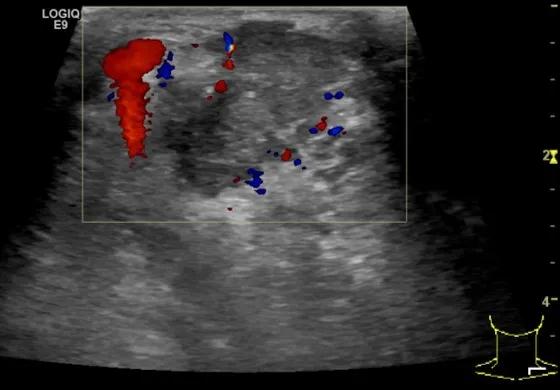

第四例是胸腺癌化妆包,术后、化疗之后淋巴结转移,肿块范围巨大,99mm*61mm,边界不清,呈浸润状,肿块包绕颈动脉,颈内静脉压闭,症状明显。由于患者放化疗也不敏感、血供非常丰富,于是采取多点姑息性消融。姑息性消融后未实现完全消融,病灶大片坏死,肿胀疼痛得到明显的缓解,后续患者未再来复查。

(病例4图例)